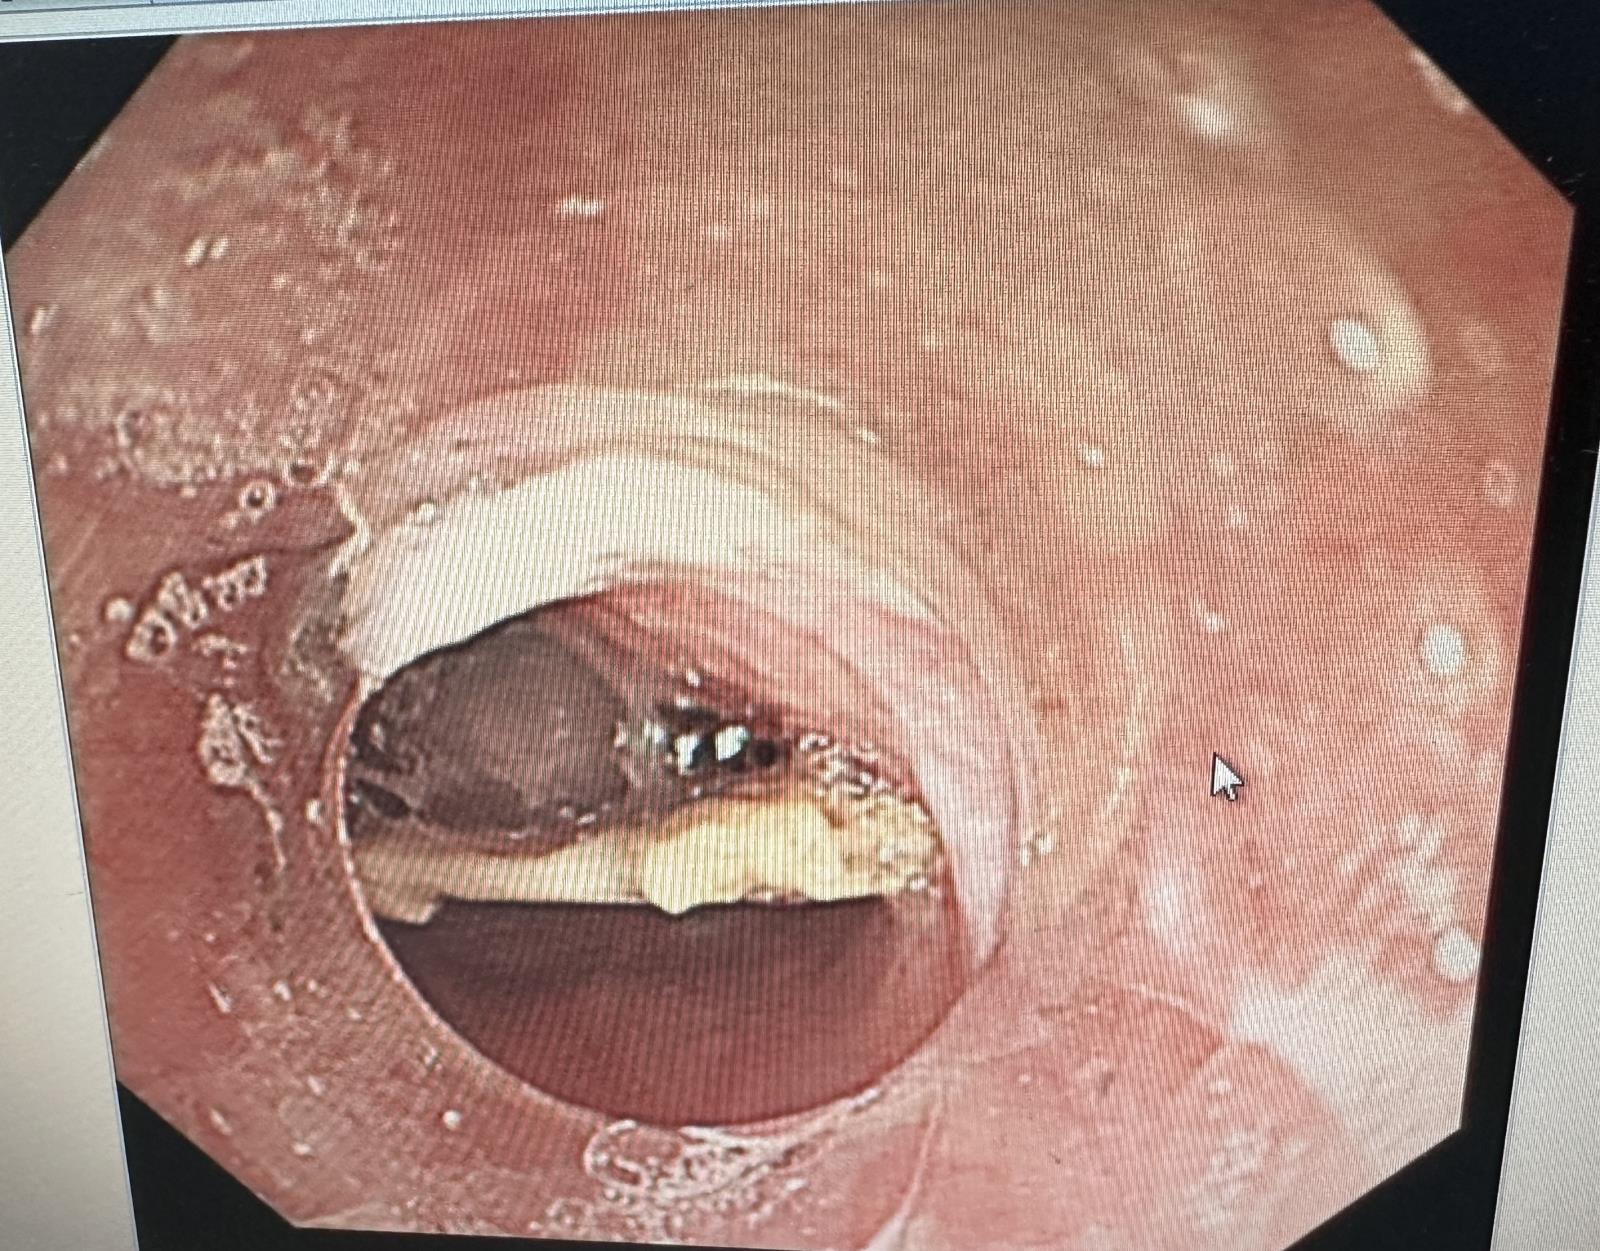

确定好治疗方案,与患者及家属沟通好治疗方案告知相关注意事项后,邓倩曦立即联系内镜室行急诊食管异物取出术,鸭骨头很快被取出,患者麻醉清醒后身体也无不适感。邓倩曦表示,“这次取异物非常凶险,鸭骨头距离门齿已经有22cm的长度,而且骨头大小约2cm左右,呈楔形,三个角也非常锋利,如果没有尽早取出,骨头发生移位,很可能导致食管穿孔或者刺破主动脉弓导致大出血,危及患者生命安全,但万幸的是患者及时就医,我们也顺利的把异物取出了。”

(图:鸭骨头较大且位置很深)